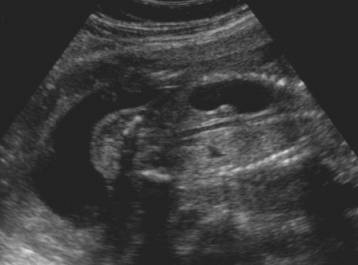

Stomach in left chest cavity

Note the absence of significant cardiac displacement.

This would be unusual in diaphragmatic hernia.